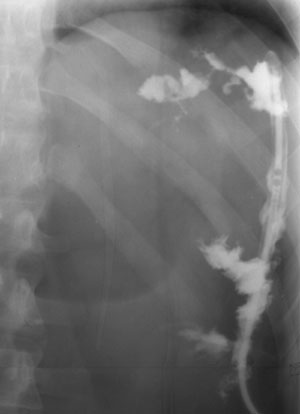

Рис. 1. По дренажной трубке в свищевой ход введено контрастное вещество (Слева). В толстую кишку (per rectum) введен воздух (Справа). В просвете толстой кишки определяется контраст, что свидетельствует о наличии толстокишечного свища.